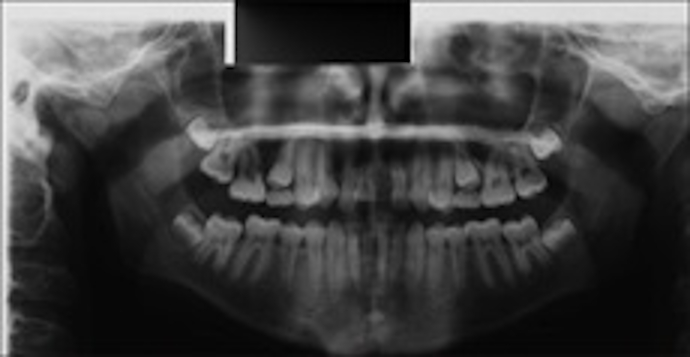

Figure 2: Orthopantograph confirms the presence of all permanent teeth except the upper left central

Figure 2:

Orthopantograph confirms the presence of all permanent teeth except the upper left central